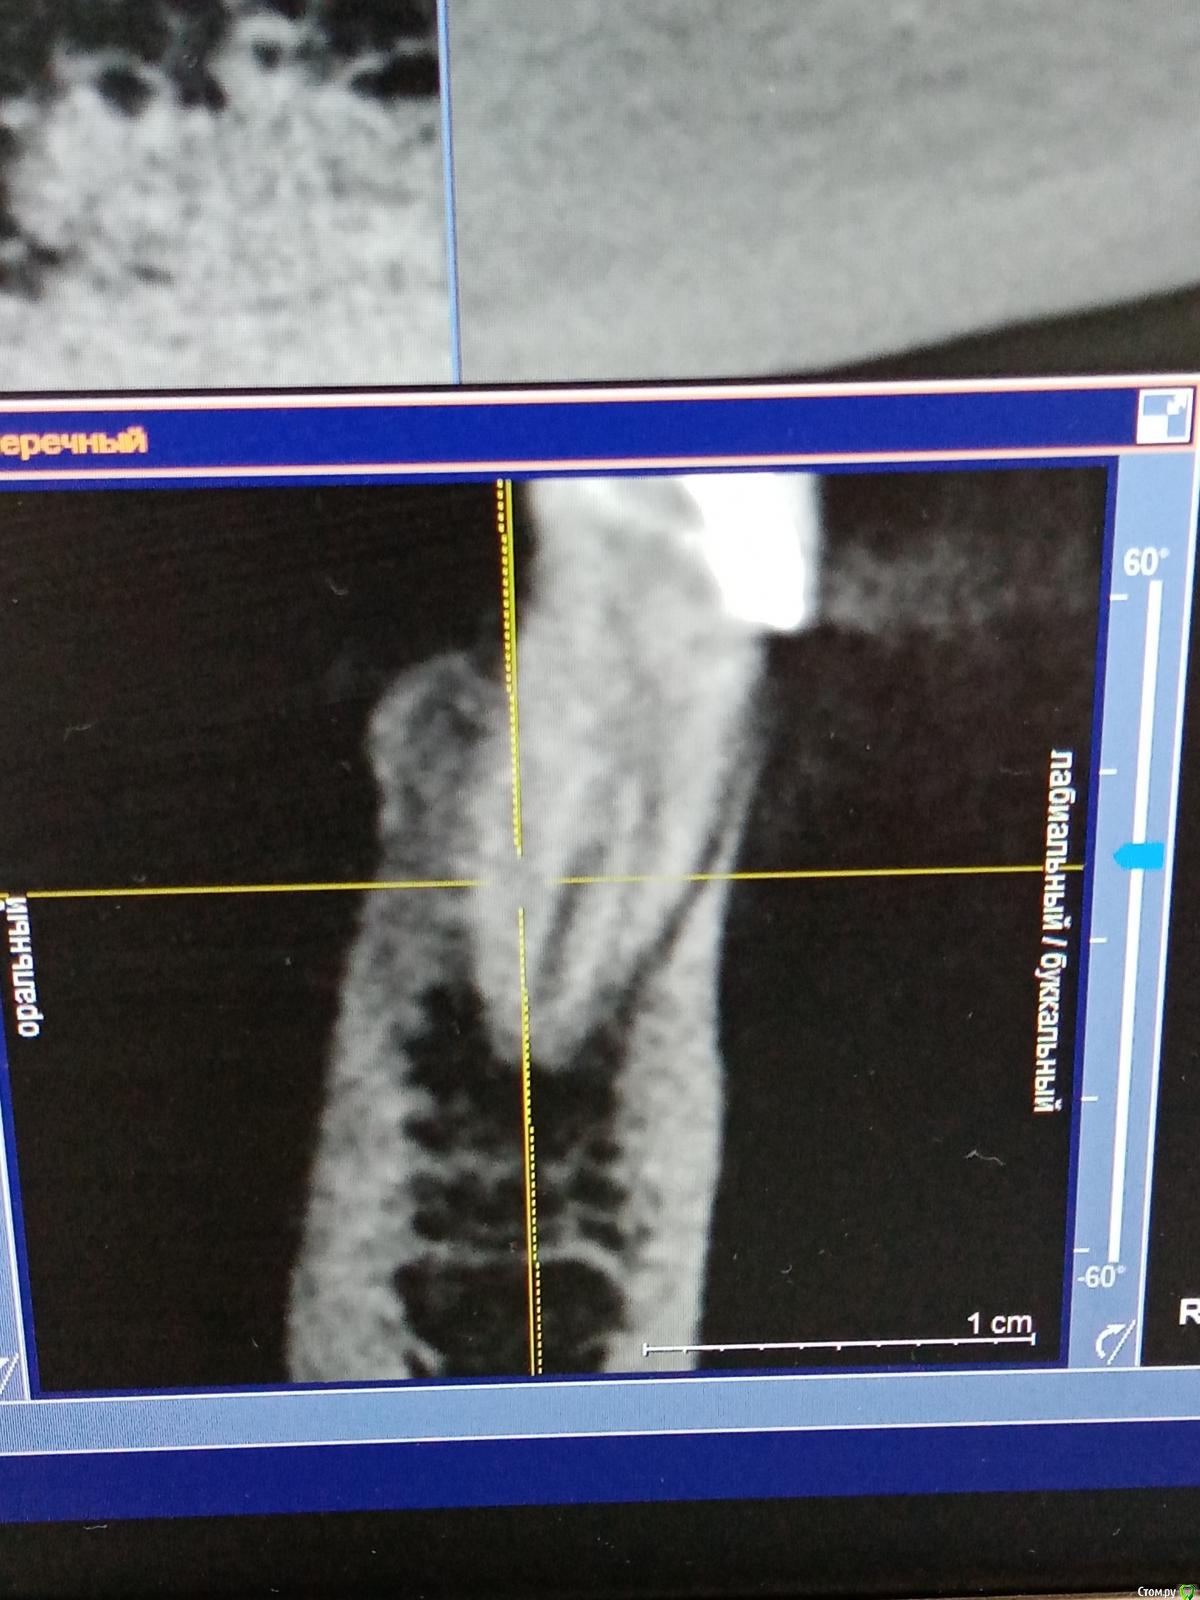

Raimar Опубликовано 30 июня, 2020 Поделиться Опубликовано 30 июня, 2020 (изменено) Зуб 4.5, ранее лечен, (эндо), пациентка пришла ко мне на перелечивание с острой болью, основную гуттаперча удалил,далее файл упирается, нужно ли пытаться распломбировать маленькие канальцы? Изменено 30 июня, 2020 пользователем Raimar Ссылка на комментарий

vse32 Опубликовано 1 июля, 2020 Поделиться Опубликовано 1 июля, 2020 Не, кт уже вижу. По-хорошему прямо надо каналы пройти. Ссылка на комментарий